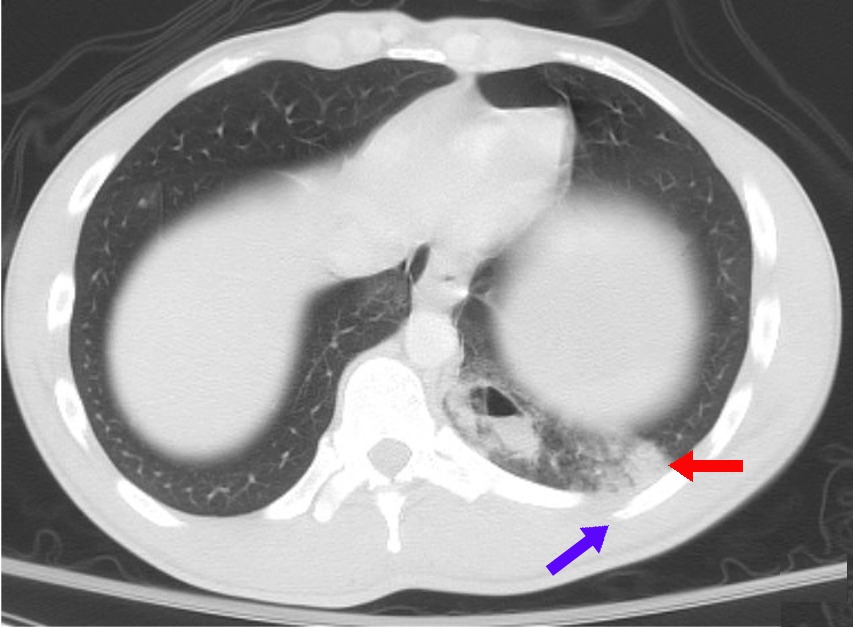

Standard adult chest phantom with lungs, heart, mediastinum, and ribs